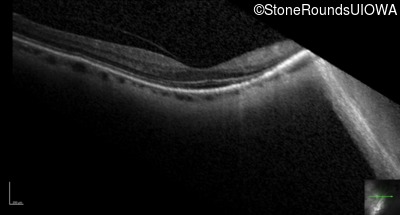

Optical Coherence Tomography - Right - 20/40 +2

Exemplar / OCT Stack